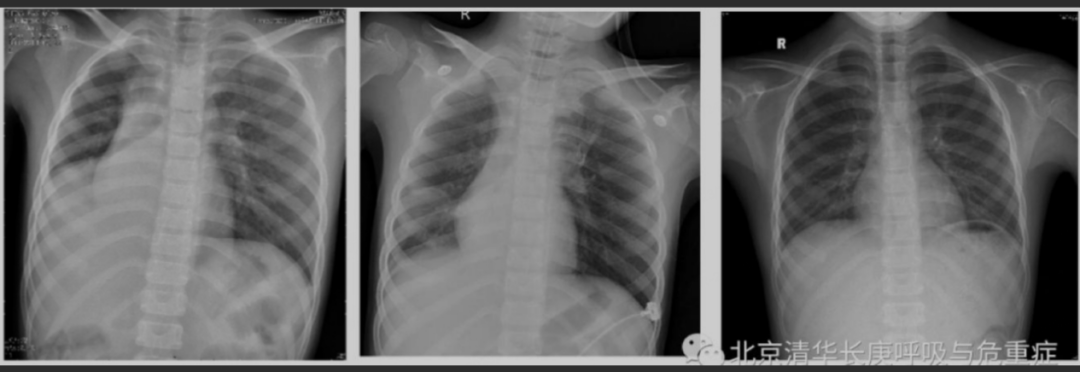

“臨牀建議”展示了牟向東團隊的救治實例。一名8歲女童因進行咳嗽、發熱、呼吸困難3天而入院,指尖血氧飽和度88%左右,心率135次/分。入院當日的胸片正位顯示右下肺不張,氣管及縱隔向右移位。後經反覆吸痰、支氣管沖洗及肺泡灌洗,患者氧飽和度逐漸恢復正常;其後複查胸片逐漸恢復正常。

術前、術後當天以及術後十天女童胸片對比

(圖源:清華長庚醫院呼吸與危重症醫學科)